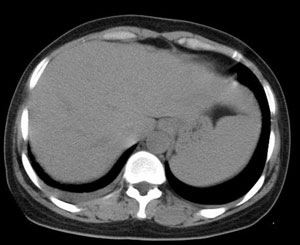

女性,30岁。

病史为胸痛20多天,无畏寒发热,无消瘦,无咳嗽咳痰。总之症状很逍遥。

临床以胸痛待查收住入院。

两肺散在分布大小不等的肿块及结节影,边缘毛糙,有分叶、毛刺,病灶密度不均匀,可见支气管充气相与空泡征。病变大多位于胸膜下,可见胸膜凹陷及胸腔积液。气管腔静脉间可见小结节影。

病人临床仅为胸痛,暂不考虑感染性病变。

考虑多发结节型细支气管肺泡癌。

考虑肺真霉菌病;心脏增大,肺动脉增宽